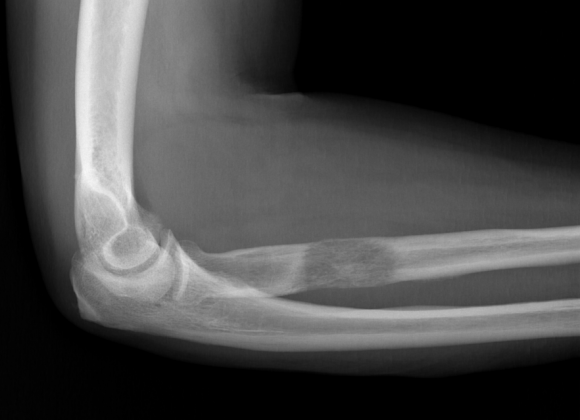

The extra-focal technique was performed under general or local anaesthesia, then close reduction was achieved by traction and counter traction and then with proper flexion the reduction was achieved in all cases under fluoroscopy guidance. After this, we make the first stab wound through first and second extensor compartment and after mobilization of underlying tendons and soft tissue we inserted the first K wire through radial styloid and cross the fracture site and go through the opposite cortex about 1-2 mm. The second K wire was passed from the lunate fossa cross the fracture site piercing the opposite cortex for about 1-2mm and the third wire was again passed through the radial styloid cross the fracture site and go through the opposite cortex about 1-2 mm and distal to the piercing of the cortex done by the previous k wire inserted from the styloid. Preoperative, postoperative and 6 month follow up images of the 2 techniques is given in Figure 1.